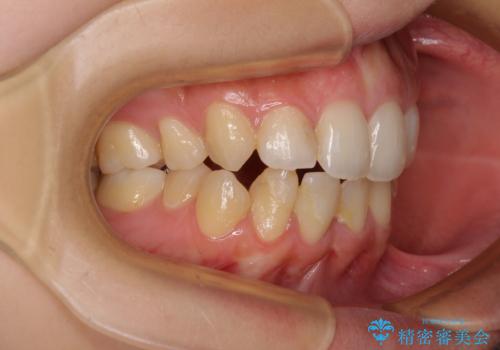

後戻りの再矯正 ワイヤー装置でデコボコと隙間を改善

- 学生時代の抜歯矯正の後戻りが気になり、再矯正を希望して来院された患者様です。

マウスピース矯正は継続する自信がなく、気になるところを短期間で改善したいとのことで、ワイヤー装置にて矯正治療を行うこととしました。

詰め物で隠していた下顎前歯の隙間は、歯軸を改善することで詰め物を除去しても隙間が目立たなくなりました。

まだ改善したいところはありましたが、患者様自身は大変満足されたとのことで、治療を終えることとなりました。